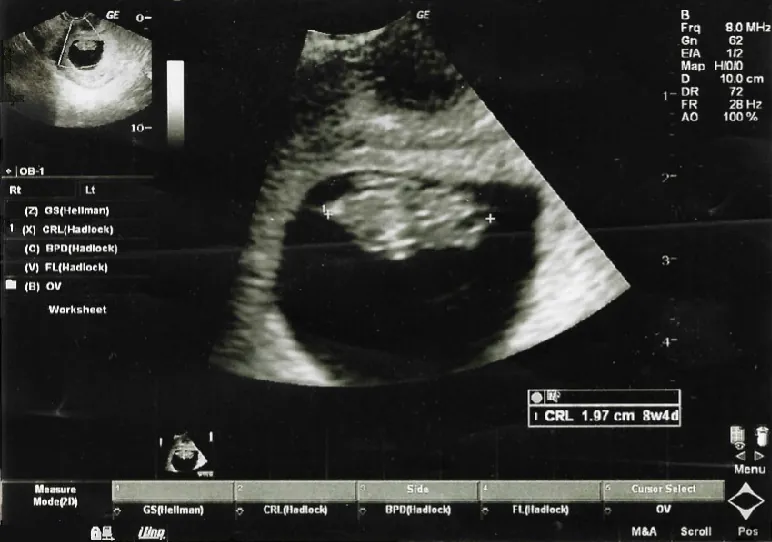

During an abdominal ultrasound exam, the gel is spread over the abdomen, and the ultrasound technician moves the transducer over the abdomen to produce the picture (Figure 13.2). The patient can be positioned to see the images if desired. The patient may be asked to come to the ultrasound exam with a full bladder to help displace the intestines and evaluate the uterus with better visibility.

Figure 13.2 First Trimester Ultrasound First-time parents may feel disappointed or concerned that the ultrasound image early in pregnancy does not “look like a baby.” The nurse can provide reassurance while teaching about fetal development. (credit: “First trimester ultrasound” by Robyn Alvarez/Flickr, CC BY 4.0)